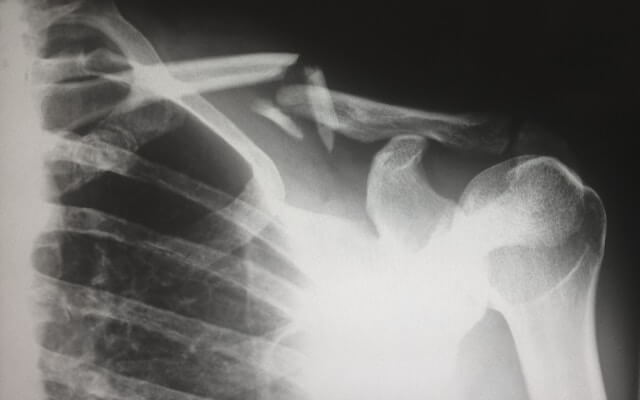

겨울철 눈이 오거나 빙판길이 있는 곳을 걷다가 미끄러질 경우 넘어지거나 엉덩방아를 찧게 될 수 있는데요. 이런 경우 건강한 성인이라면 고통보다 큰 부끄러움을 느끼고 서둘러 일어날 수도 있겠지만, 연세가 있어서 뼈가 약하시거나 특히 골다공증이 심한 환자분들 같은 경우에는 고관절 골절로 이어질 수 있습니다. 특히 고령의 골다공증 환자인 경우 이렇게 고관절 골절이 될 경우 회복이 되지 않아 심할 경우 사망에 이를 수 있습니다. 이번 시간에는 골다공증에 대해서 알아보도록 하겠습니다.

골다공증의 가장 흔한 증상 중 하나로, 가벼운 충격이나 낙상으로도 쉽게 골절이 발생할 수 있습니다. 특히 손목, 척추, 엉덩이 골절이 흔합니다. - 통증